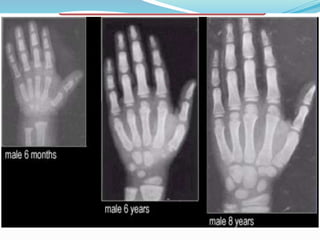

Skeletal development refers to the development of the human skeletal system from the early days of pregnancy until the bones have reached full development in late puberty . and purpose—parents can help a child with skeletal abnormalities develop positive body image and confidence in his or her abilities. A child's chronological age, determined by their birthdate, does not always align with their skeletal age, which reflects the biological maturity of their bones. While most children follow a predictable growth pattern, variations in skeletal development can reveal important insights about overall health and future growth potential.

They occur at 6-month intervals of skeletal age from 11 years in girls and 13 in boys. The fully fused olecranon occurs at skeletal age of 13 in girls and 15 in boys and marks the deceleration of growth velocity. 9. Determination of skeletal age using the Modified Tanner-Whitehouse III Skeletal Maturity Assessment (Table 1.2 and Fig. 1.12)

Purpose of review: The purpose of this review is to summarize the recent clinical findings surrounding the muscle-bone relationships in children, while considering muscle adiposity, endocrine factors, and lifestyle influences (i.e., diet and exercise) involved in pediatric musculoskeletal development. Recent findings: Positive relationships between cortical bone geometry and muscle mass, size Children have growth plates in each long bone. A growth plate is an area of soft bone at each end of the long bones. Growth plates allow the bone to grow as the child grows. The growth plates fuse by the time a child is 14 to 18 years old. CT evaluation of timing for ossification of the medial clavicular epiphysis "The clavicle is the first bone to ossify in the developing embryo and the last to complete epiphyseal union. It is the latter sustained period of growth that has attracted the interest of skeletal biologists and forensic practitioners alike, who collectively recognize the important opportunity this bone affords to